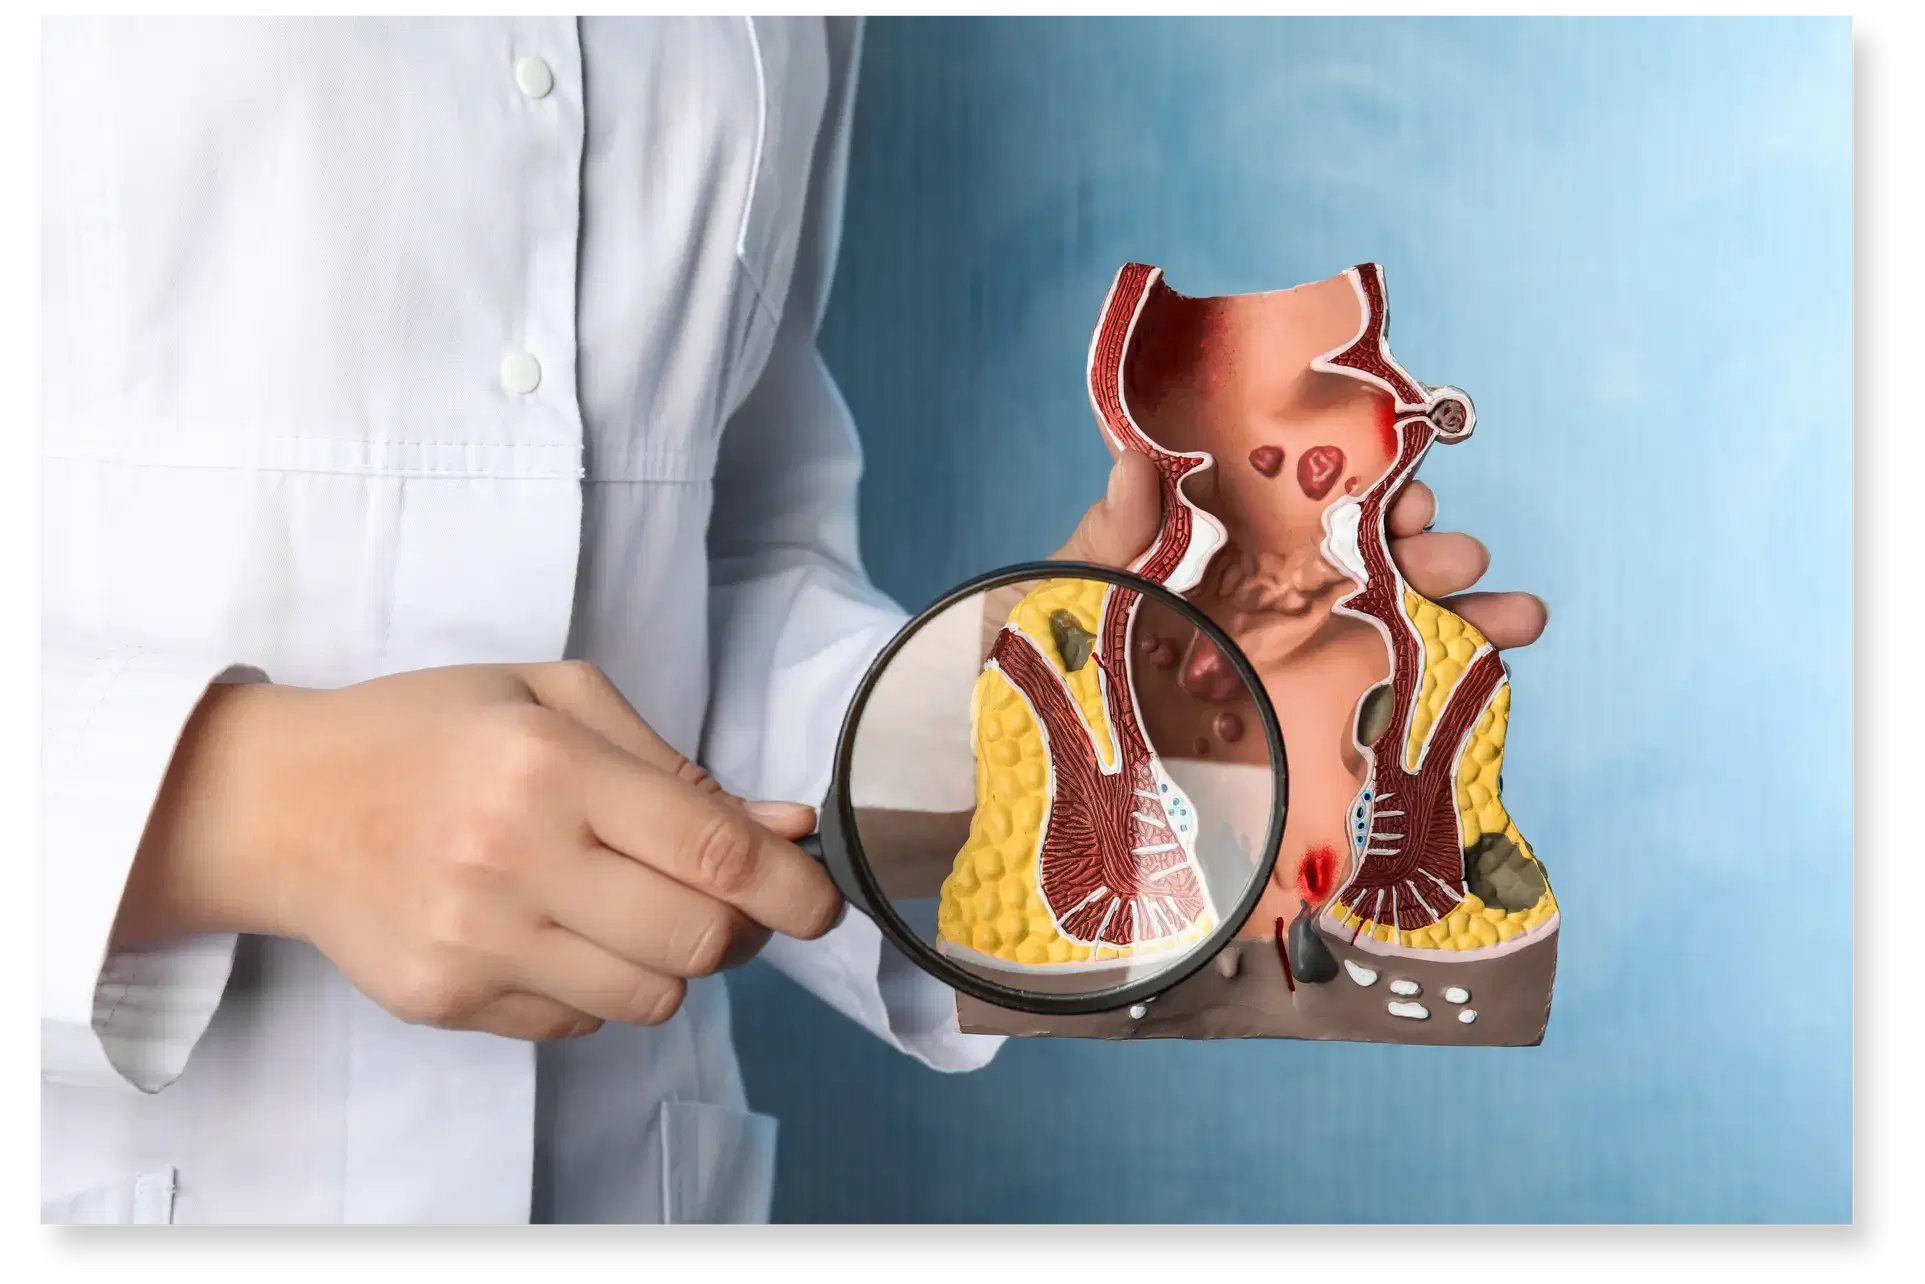

Anal Fistula Treatment in Vijayawada

At Vijayawada Gastro Centre, we offer specialized care for anal fistula using advanced diagnostic and minimally invasive treatment methods. An anal fistula is an abnormal tunnel near the anus that can cause pain, swelling, and discharge if untreated. Our experts use clinical examination, MRI fistulogram, and endoanal ultrasound for accurate diagnosis. Treatment options include laser fistula surgery, fistulotomy, seton placement, and the LIFT procedure for complex cases. With experienced gastroenterologists, state-of-the-art facilities, and personalized care, we ensure safe, effective, and faster recovery for every patient.